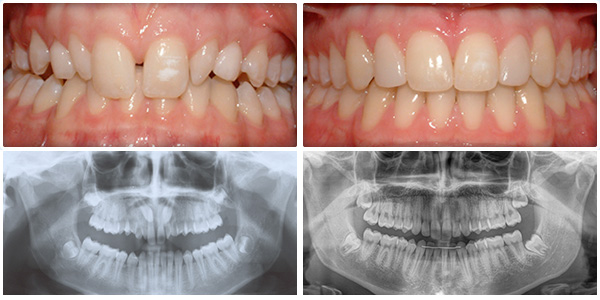

Initial Consultation

Initial Consultation